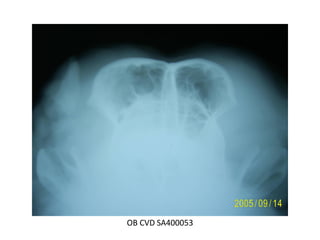

Posición

ventrodorsal

Proyeccion para el

Posiciónamiento

de la bulla

timpanica

OB CVD RX POSICION BULLAS OSEAS 4

OB CVD 9 BULLAS OSEAS

OB CVD SA400053